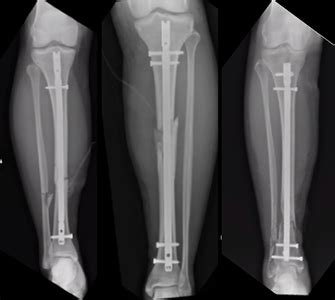

Tibia And Fibula Fracture Recovery Time